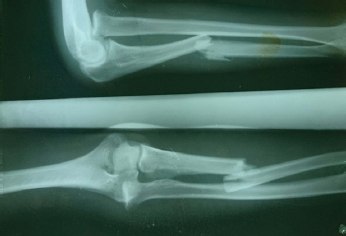

Radial head was palpable anteriorly and no supination pronation was present. There was no flexion and extension at elbow. There was no neurovascular defect. On skiagrams [Table/Fig-1], there was diaphyseal fracture of ulna with anterior angulation and radial head was dislocated anteriorly. Thus, it was labelled as Bado type I monteggia fracture dislocation.

Preoperative x-rays showing Bado type I monteggia fracture dislocation.